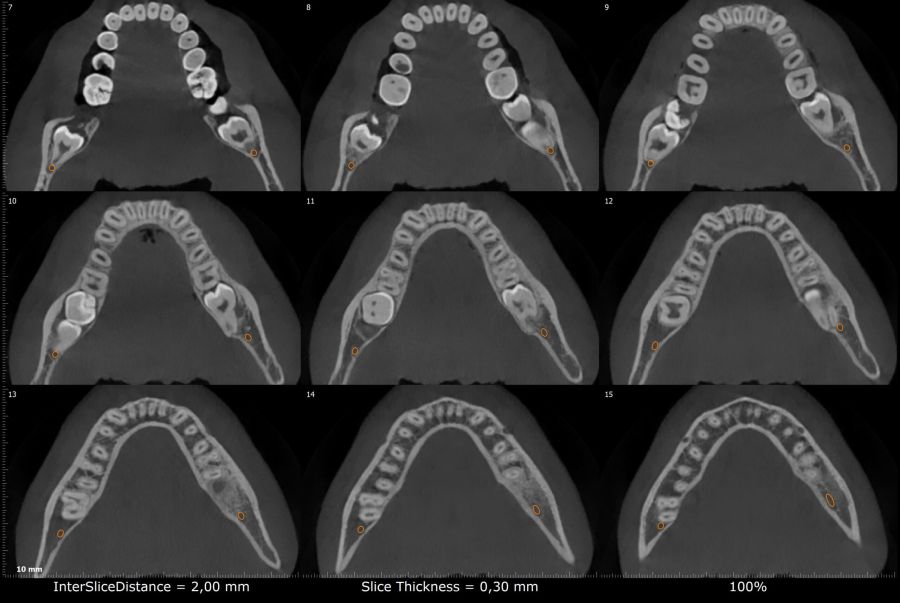

Métodos: Se presenta el caso clínico de un paciente varón de 18 años en el que, tras la realización de una CBCT de la arcada mandibular, se observó la retención de los segundos molares mandibulares permanentes junto con los terceros molares mandibulares.

Conclusiones: La retención del segundo molar mandibular es un hallazgo creciente en jóvenes y requiere un diagnóstico precoz para evitar complicaciones, siendo la CBCT la herramienta diagnóstica más precisa para evaluar la posición y riesgos asociados. Las opciones terapéuticas son diversas y siempre deben individualizarse según la anatomía, el pronóstico y las características del paciente.

Methods: We present the case of an 18-year-old male patient in whom, after performing a CBCT of the mandibular arch, retention of the permanent mandibular second molars was observed, along with the mandibular third molars.

Conclusions: Retention of the mandibular second molar is becoming more common in young patients and needs to be diagnosed early to avoid complications. CBCT is the most accurate tool to assess the tooth position and possible risks. Treatment options vary, and they should always be based on the patient’s anatomy, prognosis, and individual characteristics.